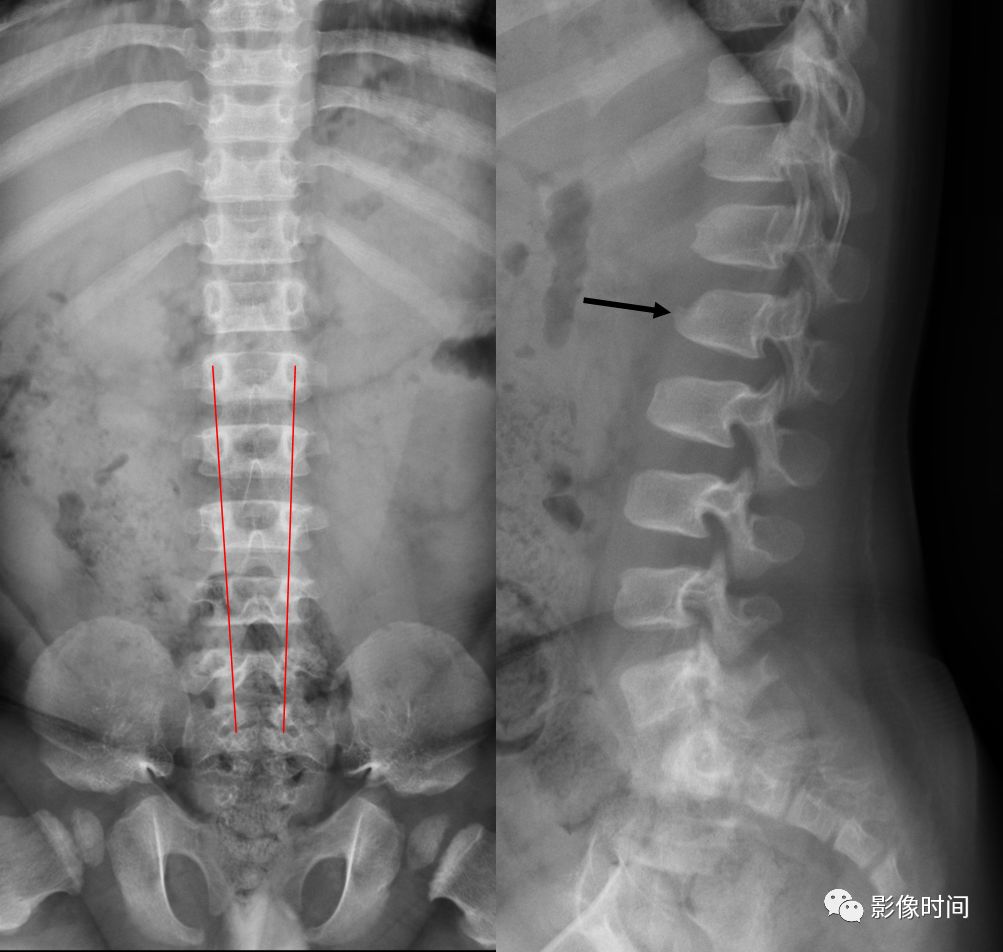

5倒置拿破仑帽征

倒置拿破仑帽征(inverted napoleon hat sign),亦有译为反拿破仑帽征

倒置拿破仑帽征是指在腰椎正位 X 线片中,腰 5 与骶 1 的投影轮廓重叠,形似倒置的拿破仑帽(蓝箭)。其中帽子的边缘是腰 5 的横突形成,而帽子的圆顶是由腰 5 的椎体投影构成。

本征象主要用于描述腰 5 椎体前滑脱(这种滑脱通常为先天性或创伤性,退变性的少见),在腰 5 未滑脱但腰骶部显著前凸时也可以出现此征象。

典型病例

22 岁男性,腰椎侧位片可见腰 5 椎体呈梯形(黑箭头),显著向前、下滑脱(黑箭),正位片形成倒置拿破仑帽征(白箭)。

引用自:1.https://radiologykey.com/natural-history-of-spondylolysis-and-spondylolisthesis2.http://www.learningradiology.com/archives2009/COW%20381-Napoleon%20 Hat%20Sign/napoleonhatcorrect.htm